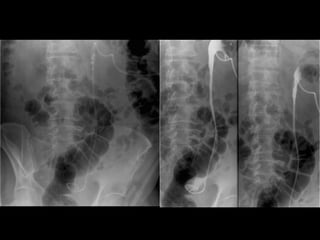

RADIOGRAFÍA SIMPLE En general delimita mal los riñones Adecuada preparación  No define trayectos ureterales No diferencia cálculos de flebolitos ni de otras calcificaciones S 45%  y  E 77% Útil en el seguimiento de la litiasis ureteral detectada por PieloTAC

PIELOGRAFÍA IV Descrita en 1923. Medios de contraste ev En caso de obstrucción el contraste puede no alcanzar al cálculo. S 75% y E 93%

Otros Radiografía renal y vesical:  S y E baja Actualmente para control de litiasis conocida Pielografía Visualiza todo el tracto urinario Cálculos: defectos de llene S 52% E 59%  Demuestra FX renal (comparar con riñón contralateral)

Otros Estudios Pielografía de eliminación:  Sensibilidad de 74% Otros: US, uretrografía retrograda, etc.